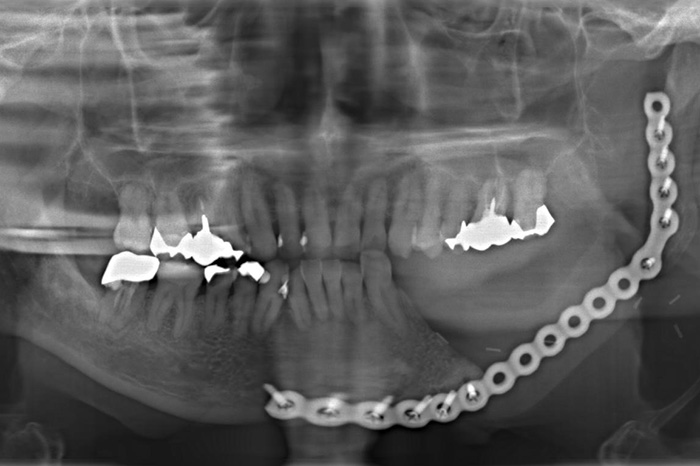

当科では、術前に歯科用3次元CTを用いて正確な診断を行い、炎症がある場合は抗生剤を用いて消炎後、抜歯を行っています。埋伏智歯の場合、歯肉粘膜の切開、骨の削除、智歯の分割、創部の縫合を必要とします。

埋伏状智歯患者のオルソパントモ写真

左側下顎水平埋伏智歯

右側下顎水平埋伏智歯

左側下顎水平埋伏智歯施術後